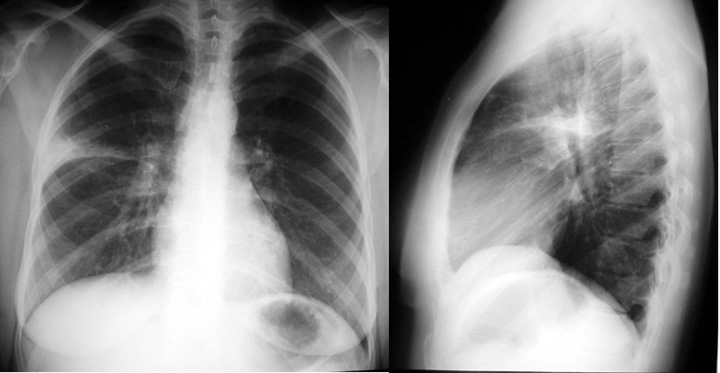

Segmental pneumonia

Right upper-lobe, anterior segment pneumonia; bronchoscopy revealed an endobronchial tumor in the anterior segment of RUL.